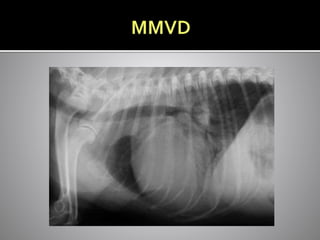

 Myxomatous mitral valve degeneration

 Middle aged-older small breed dog

 Myxomatous degeneration

 Very common

 Small breed dogs

 Soft murmur = mild disease

 Loud murmur = mild/mod or severe ds